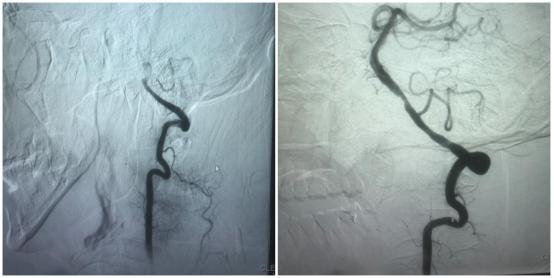

此时老李的状态逐渐萎靡 , 少言懒语 , 头晕症状更加明显 。 医生见状立即开启卒中绿色通道 , 联系医学影像科完善头颅多模态核磁共振 , 并做好患者及家属的解释工作 。 核磁共振结果显示 , 老李后脑勺的左侧椎动脉严重堵塞!在与患者家属沟通后 , 同意立即进行介入手术 。 术中发现左侧椎动脉闭塞 , 行左侧椎动脉取栓术 , 取出栓子后发现患者左侧椎动脉血管明显狭窄 , 又立即给予球囊扩张术 , 扩张狭窄血管 , 手术历时1小时 。